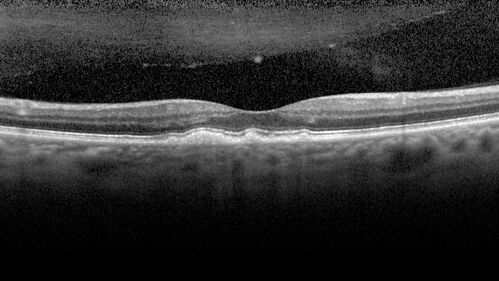

Large and Extensive Macular Drusen

64 year old female with 20/25 vision taking vitamins in for a checkup.